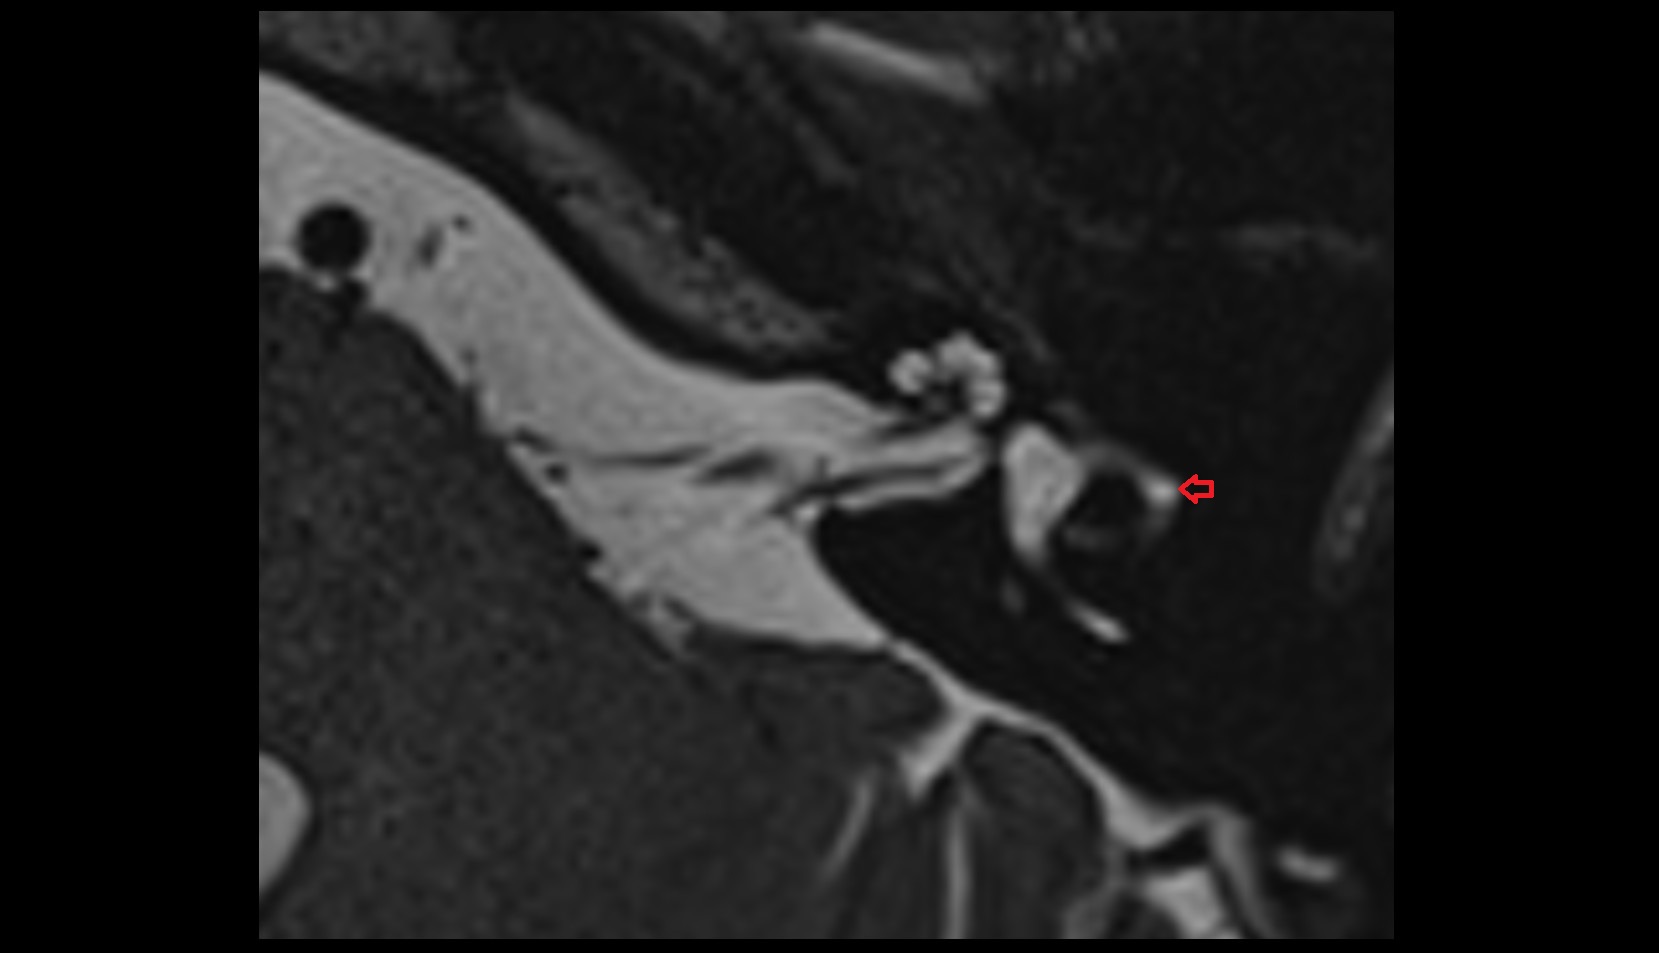

- Temporomandibular joint

- Articular disc of temporomandibular joint

- Mandibular condyle

- Mandibular fossa

- Articular eminence